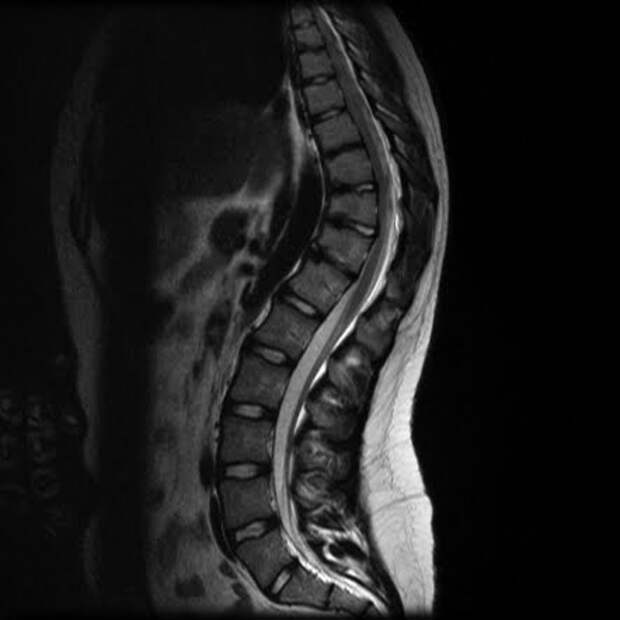

В связи с этим точная диагностика является важнейшим этапом для подбора правильного лечения.Одним из самых информативных методов диагностики кифоза является магнитно-резонансная томография (МРТ). Этот метод позволяет получить максимально четкие изображения всех структур позвоночника без использования рентгеновского излучения, что делает процедуру абсолютно безопасной даже для детей и беременных женщин.

- Высокая точность: благодаря использованию мощного магнита и радиоволн создается подробный снимок каждого позвонка, а также расположенных рядом нервных корешков, связок, мышц и других важных анатомических элементов.

- Детализация изображений: полученные снимки позволяют увидеть мельчайшие детали строения позвоночника, включая структуру межпозвонковых дисков, нервные окончания и другие элементы опорно-двигательного аппарата.